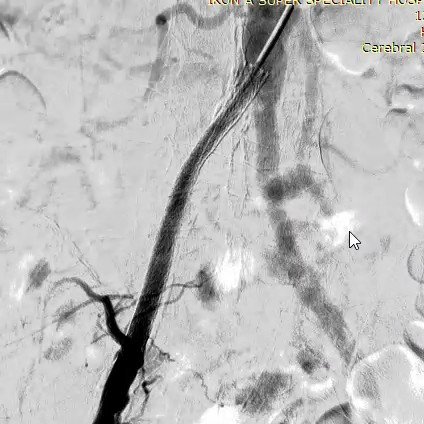

MRI/CT interpretation and Thrombectomy and stenting/ plasty for acute and recurrent stroke. Cerebral DSA

Thrombectomy – mechanical , pharmacological and combined therapy for acute stroke.

Outcomes observed in patients treated with image-guided, minimally invasive vascular procedures.

Results vary by patient and condition. Images are for educational purposes only.